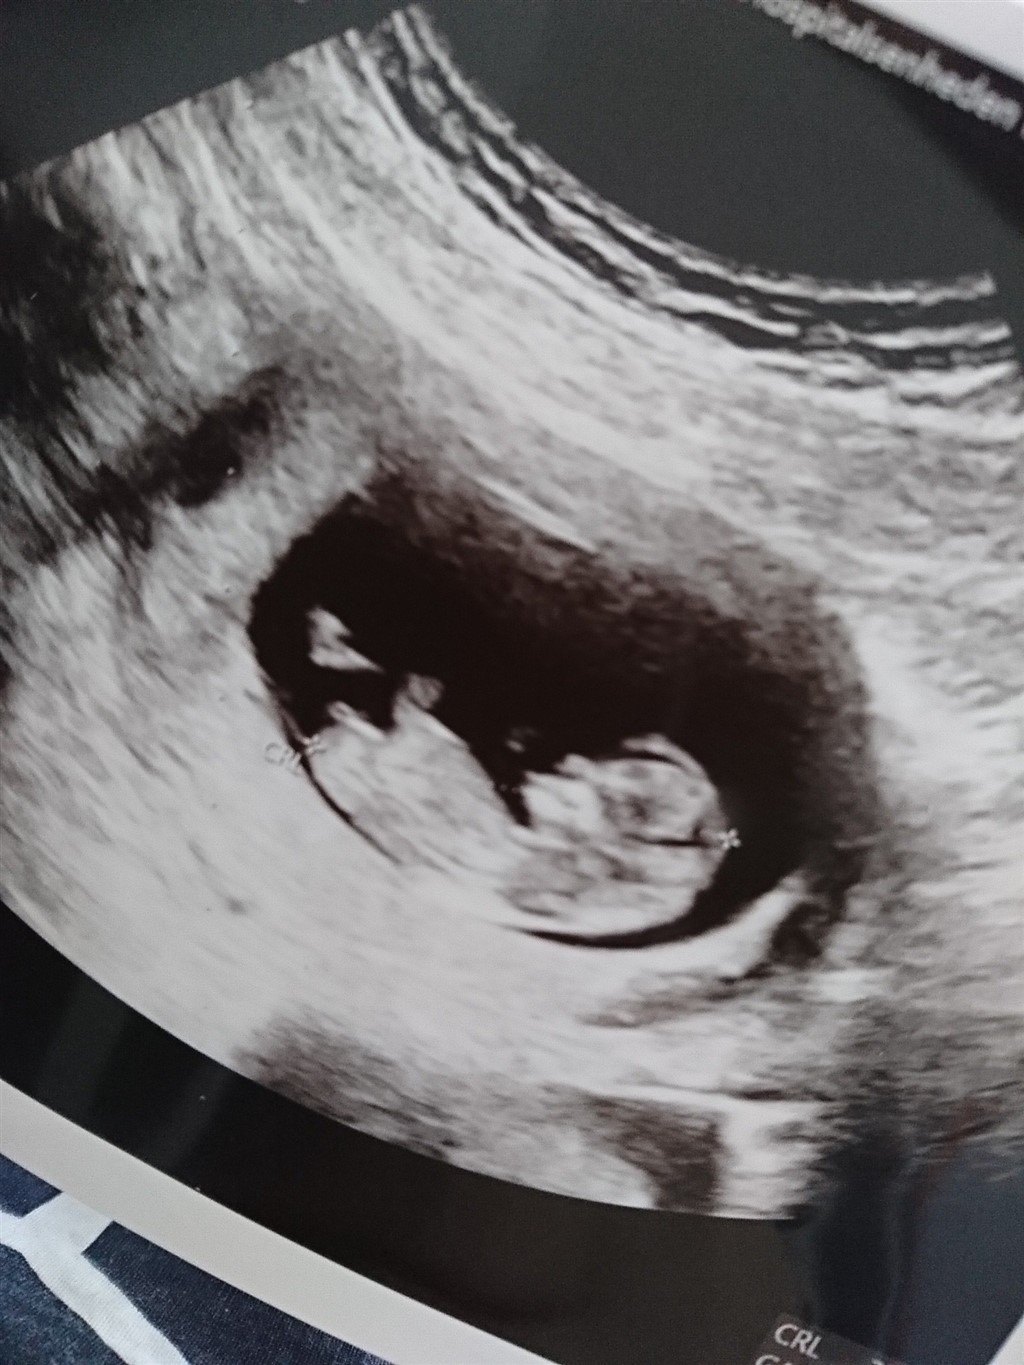

Så fik vi overstået moderkage biopsien idag, og må vente op til 7 dage på svar

Men vi fik et lille gensyn med junior, som hjullede rundt med benene og vinkede  så nu håber vi bare på et godt svar på moderkage biopsien i næste uge, så vi kan komme til at nyde det her noget mere  og selvfølgelig kommer ud og bruge lidt penge, når vi får kønnet afvide